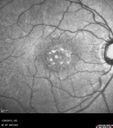

Central Serous Retinopathy 25 year old professional baseball player - Atypical - Choroidal Hypo-perfusion?551 views00000